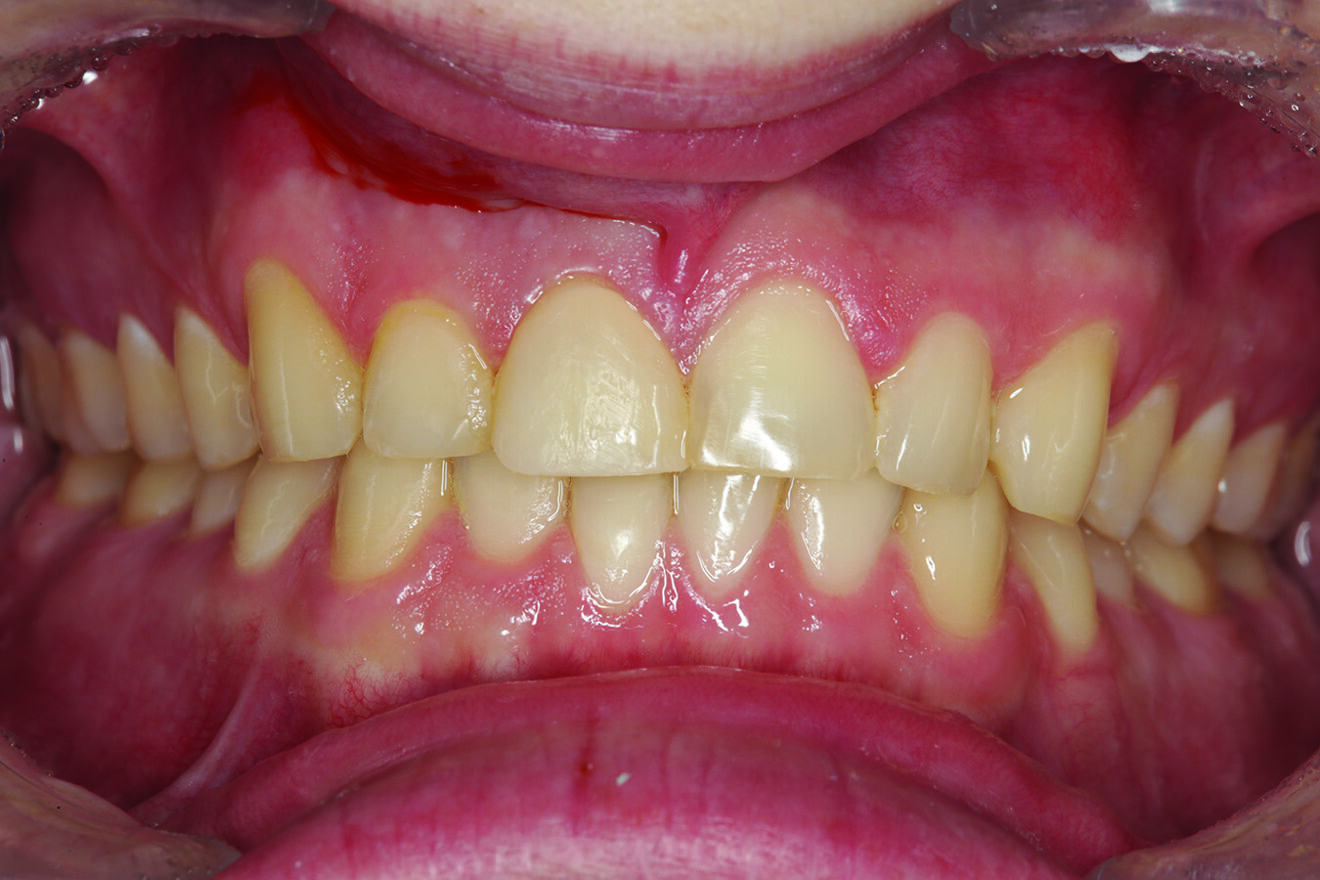

Fig. 2: Teeth in protrusive excursion, showing excessive wear on the tooth (# 41) opposing tooth #11, indicating hyperfunction and increased functional stress on the restored area.

What about the alignment of the opposing teeth? It could be observed that excessive wear was present on the incisal edges of teeth #31 and 41 (Fig. 2). From the incisal view, exten­sive wear was seen on all mandibular inci­sal edges due to occlusal disease—which is often seen yet left untreated (Fig. 3). Tooth #41 was also facially positioned so that in pro­trusive excursion it engaged the palatal surface of tooth #11 prematurely, placing addi­tional stress on both the palatal surface and inci­sal edge of tooth #11 before coupling with the remainder of the maxillary anterior segment. This demonstrates that addressing these issues restoratively involves more than just fixing a chipped composite restoration.